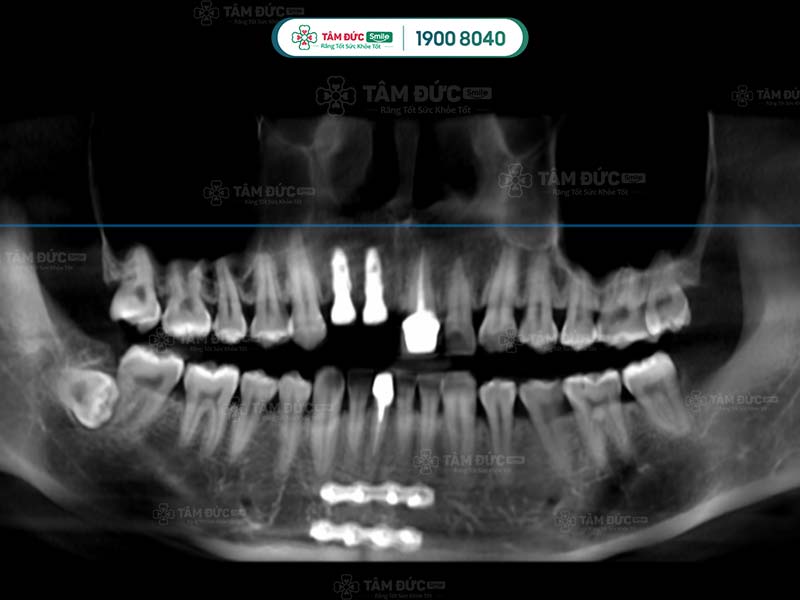

10.1. Chụp phim và tư vấn

Đây là bước quan trọng nhất trong quy trình nhổ răng khôn an toàn. Quý khách cần chụp phim X-quang để bác sĩ xác định vị trí và tư thế của răng khôn. Qua đó, bác sĩ dễ dàng đưa ra phương án nhổ răng an toàn nhất.